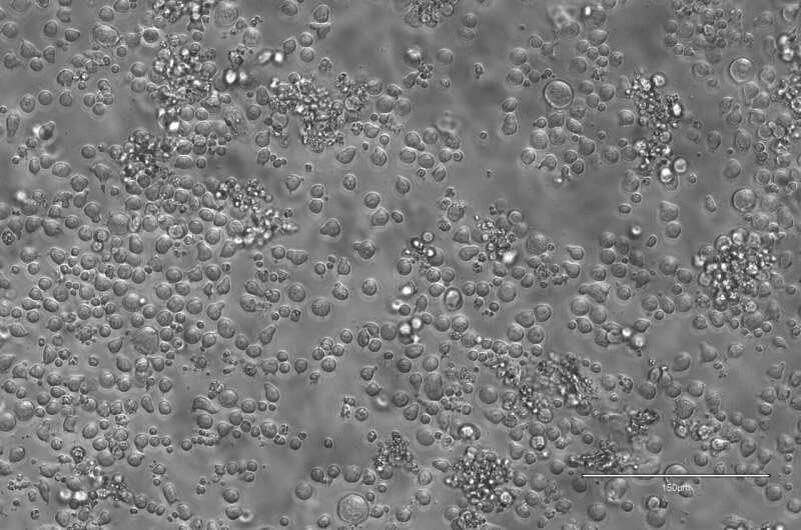

Ученые из Центра регуляции генома (Center for Genomic Regulation, CRG) и Института биомедицинских исследований (Institute for Research in Biomedicine, IRB Barcelona) разработали новый метод EPI-Clone, позволяющий отслеживать происхождение клеток крови. Вместо генетической модификации они использовали естественные эпигенетические метки — изменения в метилировании ДНК, которые работают как уникальные «штрих-коды».

Технология основана на платформе Tapestri от компании Mission Bio, адаптированной для анализа отдельных клеток. Это позволило ученым восстановить «родословную» кроветворных клеток у людей и мышей без вмешательства в геном.

Исследование, опубликованное в журнале «Nature», показало, что с возрастом система кроветворения теряет разнообразие. В молодости тысячи стволовых клеток производят сбалансированный набор кровяных телец. Однако после 50 лет количество активных стволовых клеток сокращается, и лишь несколько клонов начинают доминировать.